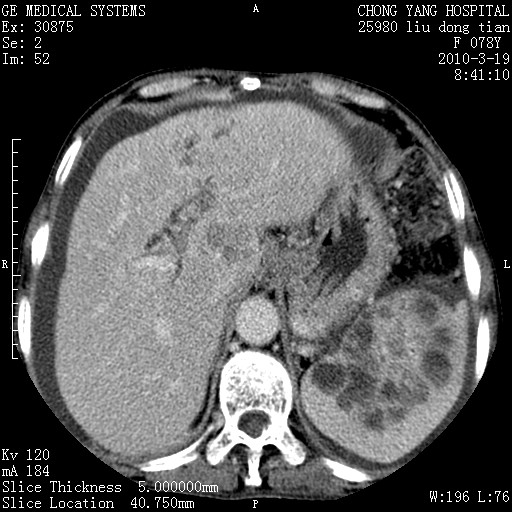

标题: CT25199:F 78Y 腹胀半年 消瘦乏力 [打印本页]

胆囊壁增厚并明显强化,胆囊癌伴多发转移瘤可能性大,淋巴瘤不除外,右肾囊肿,胸腹水.

考虑nhl,肝、脾、腹膜腔及腹膜后多发淋巴结受侵,腹水,右肾囊肿,慢性胆囊炎,右侧少量胸腔积液。

胆囊有软组织影有强化,支持胆囊癌,肝脾、腹膜后淋巴结转移。

nhl的淋巴结多围绕主动脉,而且主动脉会移位,所以不考虑nhl。

分开来讲:肝左叶、尾叶病灶有不均强化像肝癌;

脾脏病灶无强化,像多发囊肿或淋巴管瘤,不除外淋巴瘤(低强化);

胆囊增生性病变:胆囊癌,腺肌增生症,慢性胆囊炎;

肝门、胰腺头、腹膜后多个团块: 淋巴瘤,转移;

腔静脉肝内段细小有无布加可能?

一元论最好了 淋巴瘤所致改变; 胆囊癌转移不像,胆囊周围肝组织清晰,肝癌淋巴结转移?三元论都不止。

脾脏病灶像车轮 莲花,第一感觉还像包虫呢。真想全切出来一个个做病检。

最后报的胰头癌多发转移,脾脏单独考虑囊肿或淋巴管瘤。